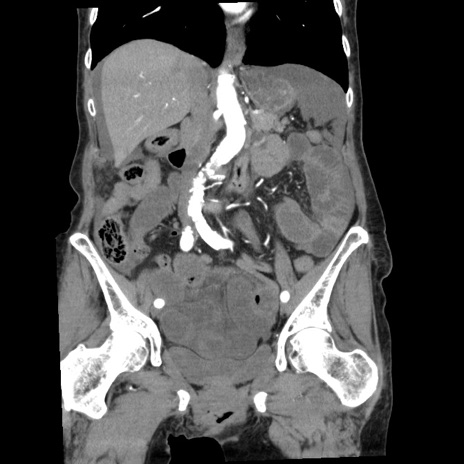

症例1(冠状断像)

症例

【症例】80歳代女性

【主訴】腹痛

【現病歴】8時間前から腹痛あり来院。

【既往歴】糖尿病、脂質異常症、子宮体癌にて子宮全摘術

【身体所見】意識清明・会話良好だが腹痛で苦悶様、全腹部にわたって反跳痛と圧痛あり

【データ】WBC 13600、CRP 0.14、LDH 224、CK 90